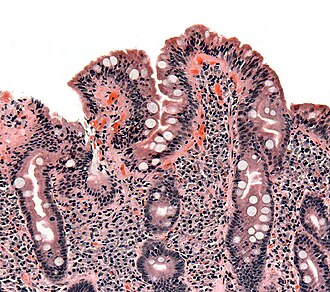

Celiac disease. H&E stain. | |

| LM | Intraepithelial lymphocytes +/- villous blunting |

| LM DDx | Giardiasis, lymphoma |

| Site | Duodenum. |

Microscopic

Features:[9]

- Intraepithelial lymphocytes (IELs) - key feature.

- Loss of villi - important feature.

- Normal duodenal biopsy should have 3 good villi.

- Plasma cells - abundant (weak feature).

- Macrophages.

- Mitosis increased (in the crypts).

- +/-Collagen band (pink material in mucosa) - "Collagenous sprue"; must encompass ~25% of mucosa.